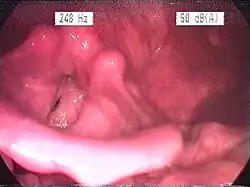

Im lupenlaryngoskopischen Bild fallen vor allem Hyperplasien der Schleimhäute überwiegend der posterioren (hinteren) Anteile des Kehlkopfes, des Ösophaguseingangs und der Rachenhinter- und Seitenwände auf. Typisch ist eine Hellfärbung und Fältelung der Schleimhäute, aufgrund der Verdickung entfaltet sich der Recessus piriformis weniger gut. Je nach Liegegewohnheiten kann durch überwiegend nächtlichen Reflux eine Bevorzugung einer Seite beobachtet werden. In neueren, experimentellen Studien konnten negative Einwirkungen des Reflux auf die Mikrostruktur der Larynxschleimhaut nachgewiesen werden. So führt der Magensaft zu einem verminderten Widerstand der Mucosabarriere mit der Folge leichteren Eindringens von Schadstoffen in tiefere Zellschichten.[1] Eine andere Untersuchung wies Veränderungen im Immunsystem der Schleimhaut (bei sogenannten Killerzellen) infolge eines Reflux nach.[2]

Standard ist nach wie vor das endoskopische Bild, auch wenn einzelne Studien gezeigt haben, dass die Befunde sehr variabel sein können und daher bei verschiedenen Untersuchern zu unterschiedlicher Interpretation führten. Als apparative Untersuchung zum direkten Nachweis eines Reflux zählt die 24h-pH-Metrie, wobei die klassischen Sonden mit Messpunkten im Magen und unteren Ösophagus nicht optimal sind, da nur ein Messpunkt im Hypopharynx den Reflux in der Zielregion erfassen kann. Daher sind spezielle Messsonden mit entsprechender Konfiguration besser geeignet. Zur allgemeinen Abklärung einer Ursache (z. B. Hiatushernie) ist eine Magenspiegelung erforderlich (siehe auch Refluxösophagitis). Auch bereits ein nicht-obstruktives Schnarchen kann refluxfördernd sein, da durch die Verlegung der Atemwege ein erheblicher Druckgradient vom Magen zum Thorax-/Halsraum entsteht.[3][4][5] Der thorakale Unterdruck bei (frustraner) Inspiration steigt erheblich an, der Magensaft wird nach oben gesaugt. Daher ist ggf. auch eine Polysomnographie im Schlaflabor, optimalerweise mit Somnoendoskopie, erforderlich.